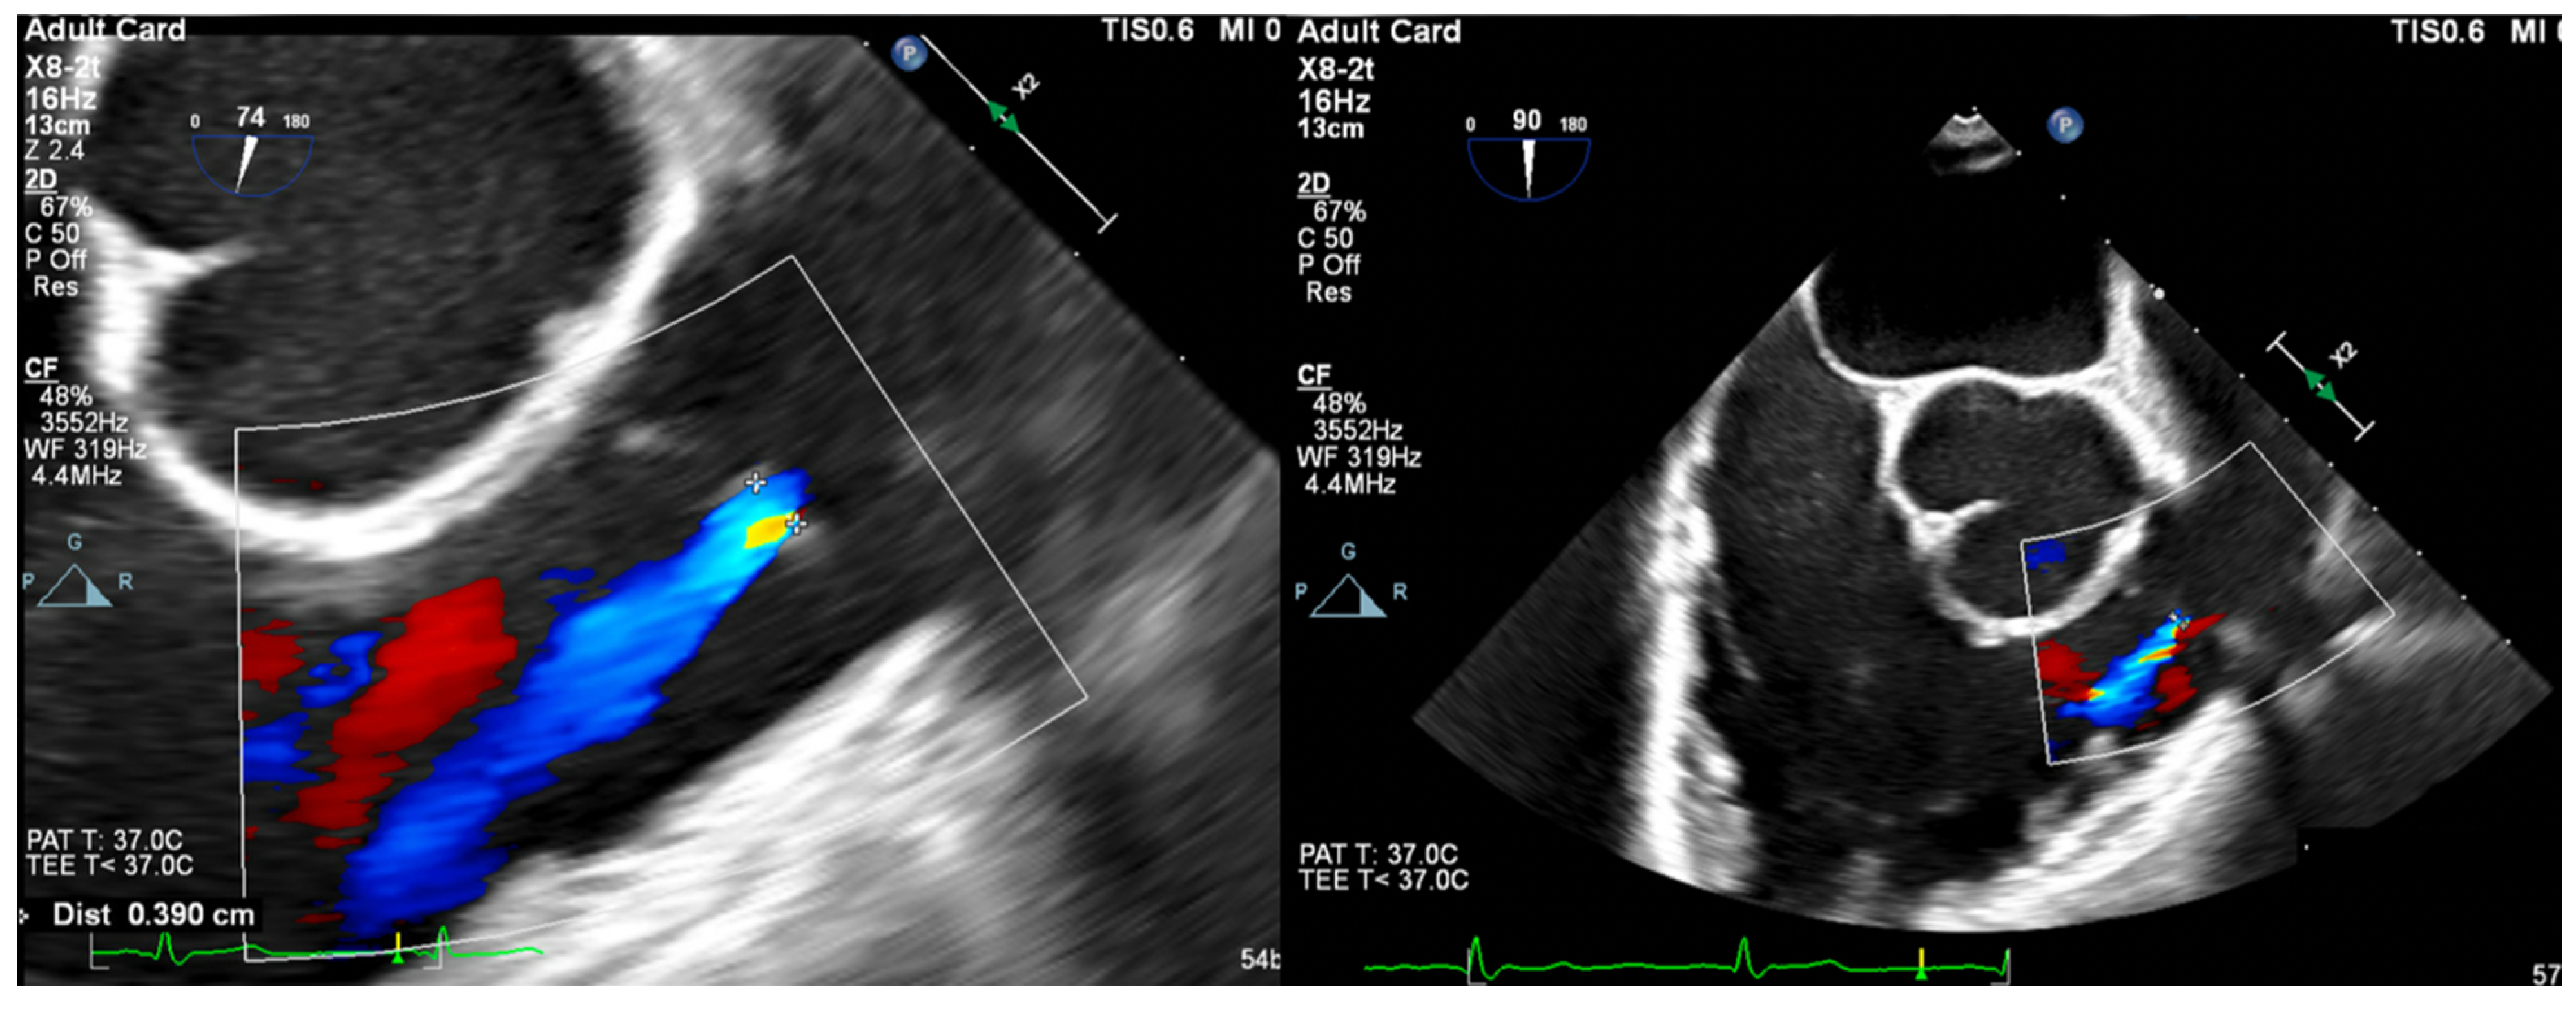

- Vena Contracta Width (VCW): Typically not used for multiple jets. Cutoffs for various grades of PR have not been validated, but most use AI cutoffs (Figure 1).

- VCW/PV ratio has been used with a value of >0.5 consistent with severe PR.

- PR Jet Width/RVOT Width: With >65% consistent with severe PR (Figure 3).